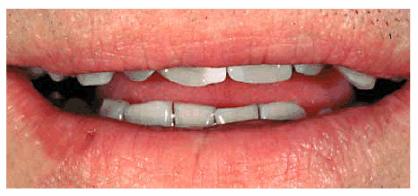

Figure 24-7B: This occlusal view shows why full orthodontic treatment was originally presented as the ideal treatment. The patient insisted on a "quick fix" solution.

TREATMENT: When teeth are as crowded as this, it is sometimes necessary

to do a vital pulp extirpation to prepare the teeth for adequate porcelain

thickness. Thus, tooth preparation and diagnostic wax-up were first completed

on the study casts (Figures 24-7C, and 24-7D). The patient was fully informed of the possibility of

endodontic therapy. The actual tooth preparation can be seen in Figures 24-7E, and 24-7F. Fortunately, the pulp had receded, so extirpation was

not necessary. Electrosurgery was completed prior to impressions to improve

access to the preparation margins. Six full porcelain crowns restored the

esthetics of the maxillary arch (Figure 24-7G), whereas composite resin bonding helped restore

mandibular esthetics. A maxillary occlusal night appliance was constructed for

the patient to wear since the patient had a history of clenching while

sleeping.